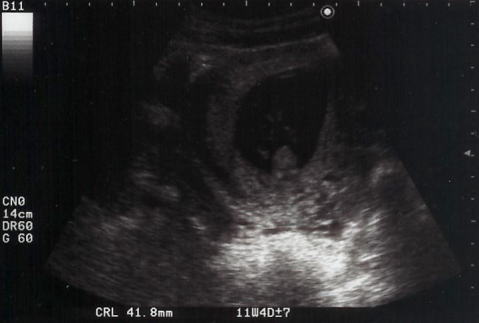

2004年10月1日(金)

11週4日

暗くて見えにくいけど、大きな頭と手が見えます。ママやパパと同じ形になりました。

写真中央で2頭身shigeruが仰向けになっている

こちらの写真はもっと判りづらい